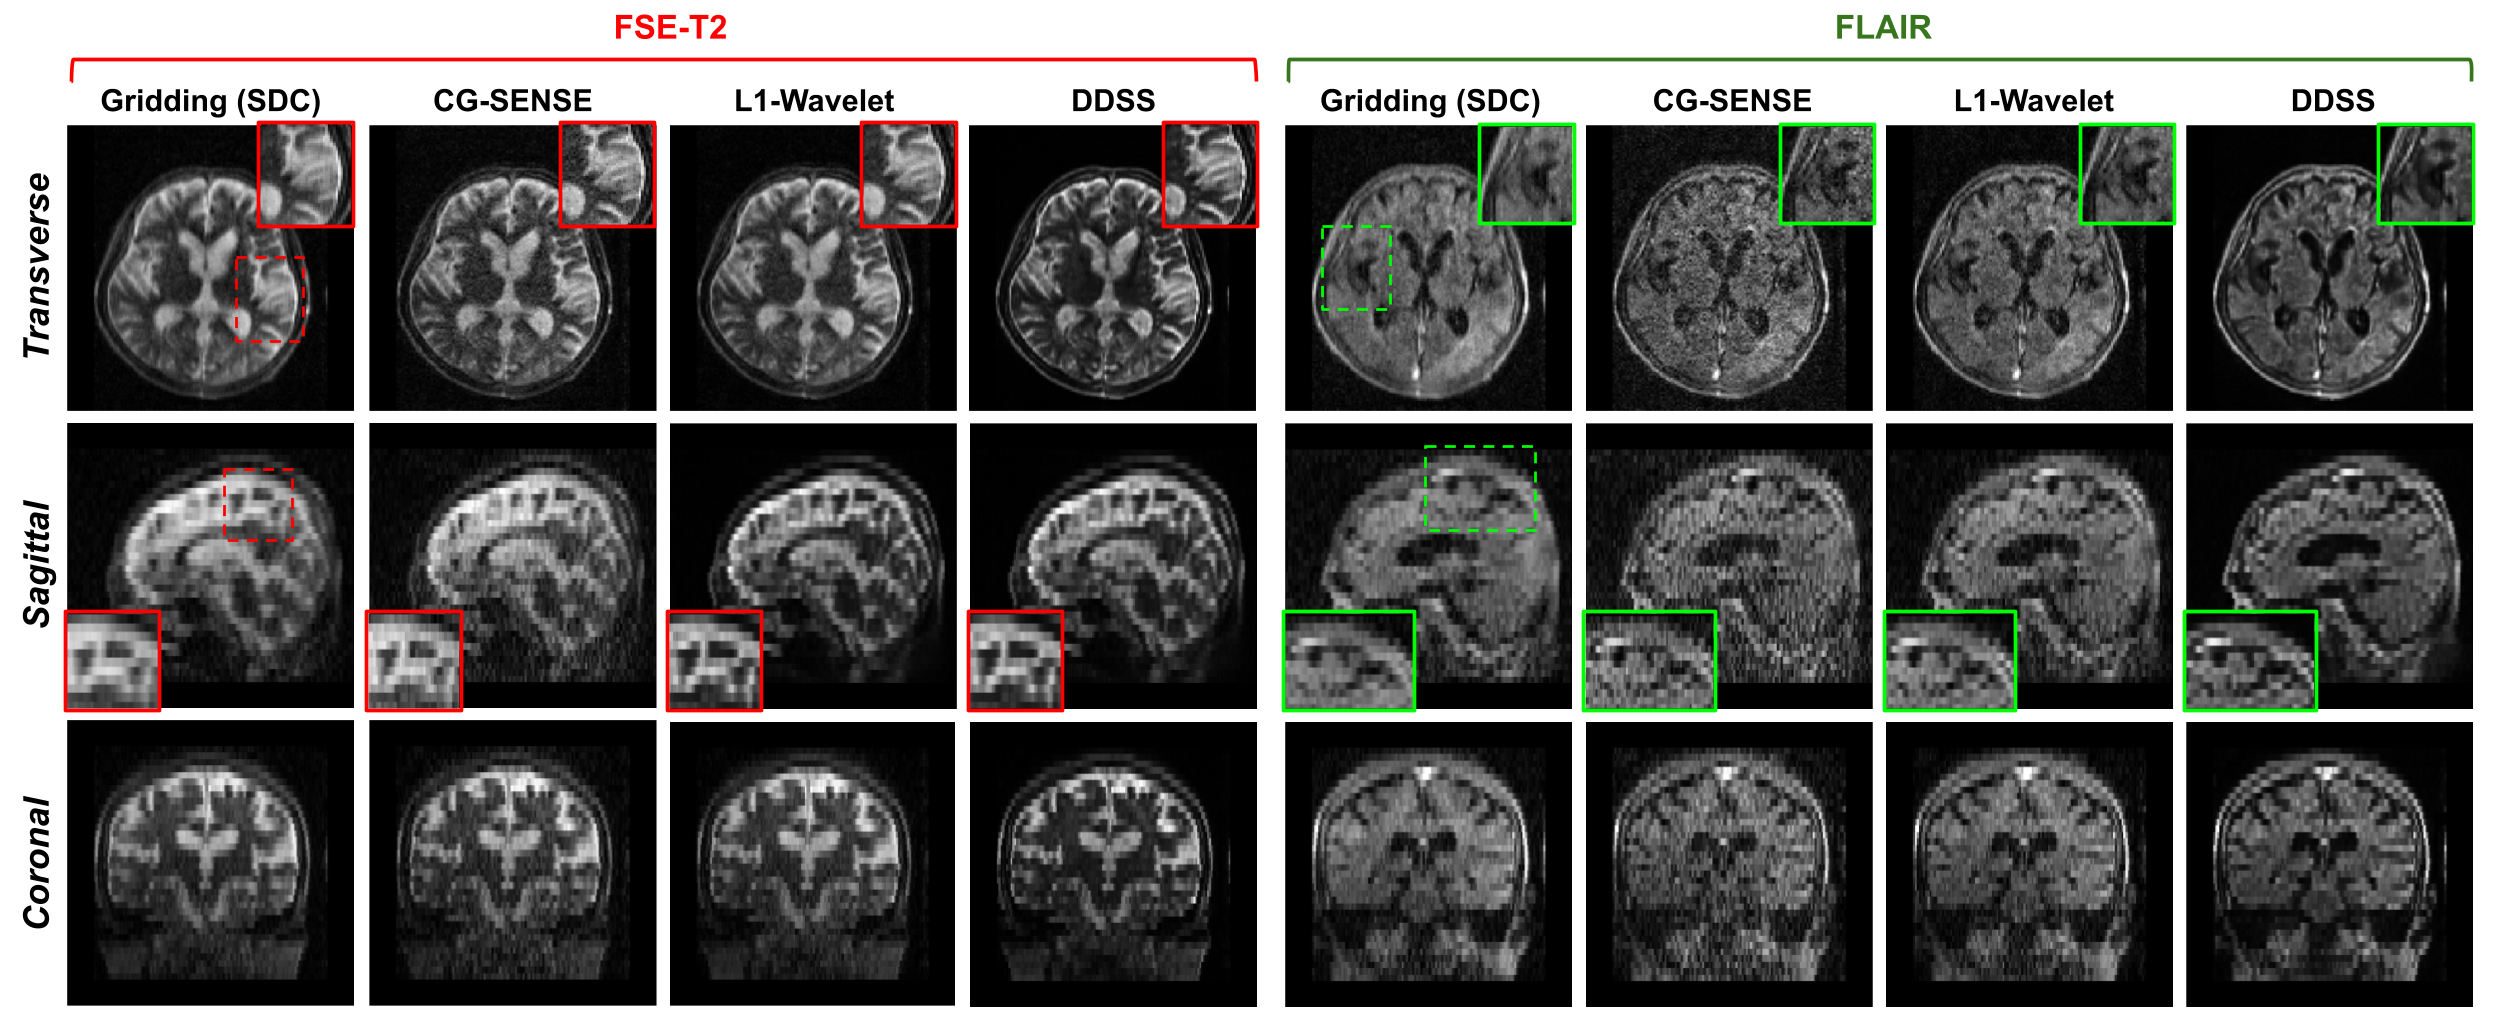

Refer to caption

Fig. 9: Qualitative comparisons of FSE-T2w and FLAIR reconstructions from the real data acquired from a low-field (64mT) MRI system. The subject was diagnosed with a hemorrhagic stroke with lacunar infarcts. The DDSS reconstruction is compared to Gridding, L1-Wavelet, and CG-SENSE [30] reconstructions of this subject.

Qualitative results are presented in Fig. 9 and Fig. 10, where we visualize results from FSE-T2w and FLAIR scans of two subjects presenting with hemorrhagic strokes. In addition to visualizing the CG-SENSE reconstruction, we also visualize the Gridding and L1-Wavelet reconstruction for qualitative comparisons. As we can see from Fig. 9 with R=2, the Gridding reconstructions suffer from blurring due to the accelerated data acquisition protocols. While the L1-Wavelet and CG-SENSE methods can reduce blurring, the proposed self-supervised DDSS reconstructions produce much sharper image quality leading to enhanced visualization of neuroanatomy. Similar observation are made in Fig. 10, where DDSS provides reconstructions with better contrast, sharpness, and lower noise under both R=2 and R=4 acceleration factors.